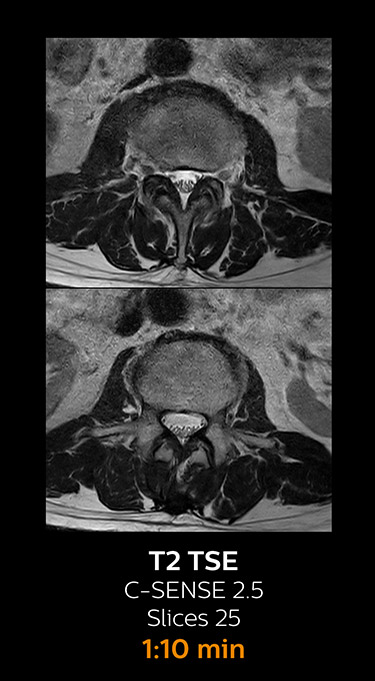

MRI examination of the lumbar spine with Compressed SENSE

Ingenia 3.0T CX

Scan time 8:17 min. (was 11:41 min. without Compressed SENSE)

With Compressed SENSE, the scan time for the routine lumbar spine examination at KNC was reduced from 11:41 to 8:17 minutes,

which corresponds to 34% reduction.